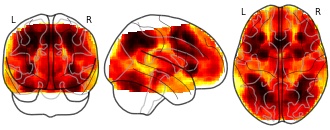

BF meta-analysis test: Working memory mean (Zero NaN)

EmailClick to copy linkLink copied Cite(2018). BF meta-analysis test: Working memory mean (Zero NaN) [Dataset]. http://identifiers.org/neurovault.image:64401niftiAvailable download formatsUnique identifierhttps://identifiers.org/neurovault.image:64401Dataset updatedMay 23, 2018License

License information was derived automaticallyDescriptionCollection description

Subject species

homo sapiens

Modality

fMRI-BOLD

Analysis level

meta-analysis

Cognitive paradigm (task)

working memory fMRI task paradigm

Map type

Other